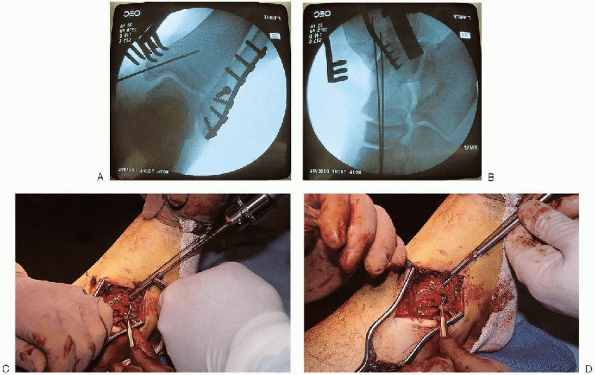

FIGURE 33-13. A:

A lag screw is placed from anterior to posterior across the fracture fragments. A gliding hole is made in the near cortex using a 3.5-mm drill. B and C: A 3.5/2.5 mushroom cap is then used to make a hole in the far cortex using a 2.5-mm drill. D and E: After measurement of the screw length and tapping of the screw tract, the lag screw is inserted. F and G: Fluoroscopic evaluation after lag screw insertion.  |